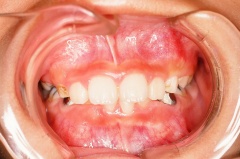

叢生(埋伏歯)

治療前 正面

乱杭歯になっています

治療後 正面

正常になっています